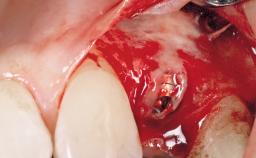

A 30-year-old female patient was referred to the office for the treatment of tooth 11. Her chief concern at the initial visit was to inquire, “Why is my tooth pink?” Upon clinical examination, it was determined that tooth 11 had a previous history of trauma and that the clinical crown had become noticeably pink in color as a result of internal resorption. This diagnosis was confirmed radiographically, indicating a large radiolucency involving the central and distal portions of the clinical crown. It was determined that restoration of this tooth was not possible, and that extraction was indicated. The presence of a mid-line diastema, which the patient wanted to reproduce, directed the treatment plan for tooth replacement utilizing a dental implant.

Placement Protocol Immediate implant placement

Tooth Site Maxillary incisor or canine

Socket Morphology Single-root socket

Socket Integrity Sufficient, with intact bone walls

Bone Volume Sufficient, with intact walls